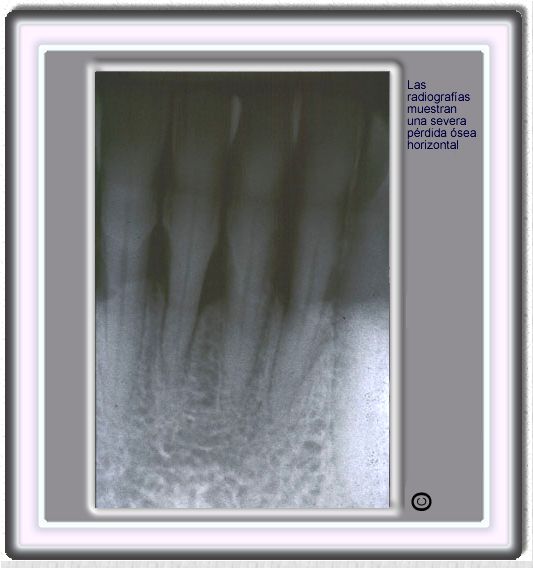

image 425